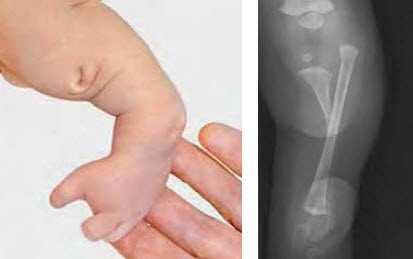

Zu den häufigsten angeborenen Längsfehlbildungen der unteren Extremität gehören die Fehlbildung des Oberschenkels (Femurdefekt) und des Wadenbeins (Fibulahemimelie). Eine Fehlbildung des Schienbeins (Tibiahemimelie) ist extrem selten (Abb.1–2). Je nach Schweregrad gibt es signifikante Beinlängendifferenzen, Achsenabweichungen und begleitende Fehlbildungen der grossen Gelenke sowie Fussdeformitäten mit fehlenden Zehenstrahlen.

Die Therapie richtet sich grundsätzlich danach, ob die betroffene Extremität überhaupt sinnvoll rekonstruierbar ist. Schwere Gelenk- und Fussdeformitäten sowie höchstgradige Beinlängendifferenzen können rekonstruktiv-chirurgische Massnahmen infrage stellen, so dass orthoprothetisch vorgegangen werden muss (Abb. 3–5). Ist ein rekonstruktives Verfahren möglich, ist zunächst dafür Sorge zu tragen, dass insbesondere an den benachbarten Gelenken möglichst stabile Verhältnisse für bevorstehende Verlängerungsoperationen geschaffen werden.